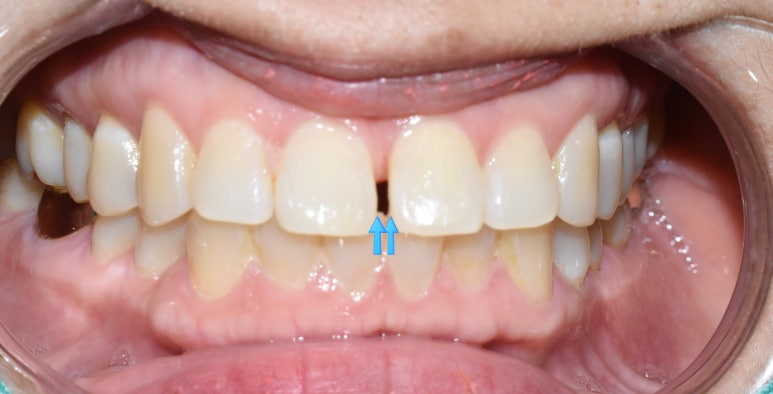

앞니 틈새를 매꾸는 레진치료는

일반 충치치료와 다르게

색도 티가 나면 안되기 때문에

흰색도 같은 흰색이 아니라 색깔 및 투명감도 굉장히 신경을 써야하고,

공간도 신경써야하고(옆 치아와의 contact 부위 까지 신경써야 하는),

매끄러움,거칠기까지 신경써야하는

일반충치보다 훨씬 손이 많이 가고 어려운 치료입니다.